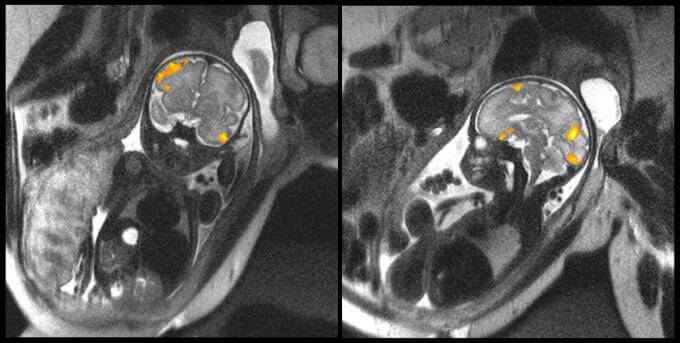

Dans l’image ci-dessus, on peut voir la résonance magnétique d’un fœtus de 20 semaines et un autre de 40 semaines. Ce sont des images qui ont été données par la faculté de Médecine de l’Université d’État de Wayne (Michigan, États-Unis) qui montrent clairement l’activité cérébrale de ces deux bébés dans l’utérus de leur mère.